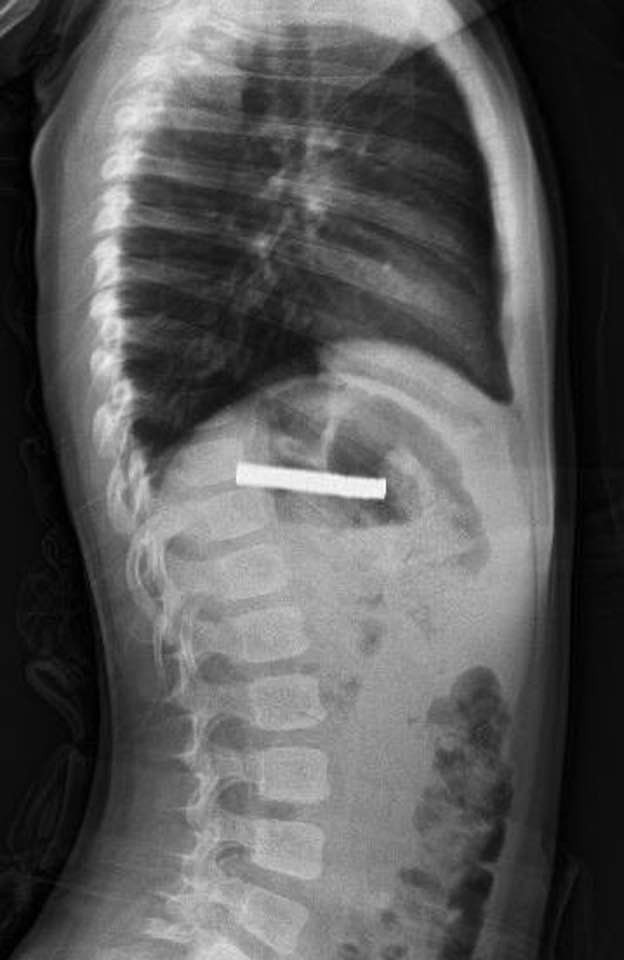

YEMEK BORUSUNDA TESİT EDİLDİ

Hastanede, FÜ Çocuk Gastroenteroloji Hepatoloji ve Beslenme Bilim Dalı Başkanı Prof. Dr. Yaşar Doğan tarafından yapılan tetkiklerde mıknatısların yapışarak çocuğun yemek borusunu tıkadığı tespit edildi.

Yapılan operasyon hakkında bilgi veren Doğan, "Tabi bu mıknatıslar uzun süre hastanın yemek borusunda kaldığı için biraz hasar bırakmıştı. Çok güçlü mıknatıslardı. İşlemin kolay yapılabilmesi için mıknatıslar yemek borusundan mideye alındı, mideden özel bir fileyle çıkarıldı. İşlemden sonra hastayı gece boyunca gözlem altında tuttuk. Sabah da aile kendi isteğiyle çıkarmak isteyince, hastanın da genel durumu iyi olduğundan taburcu ettik." dedi.